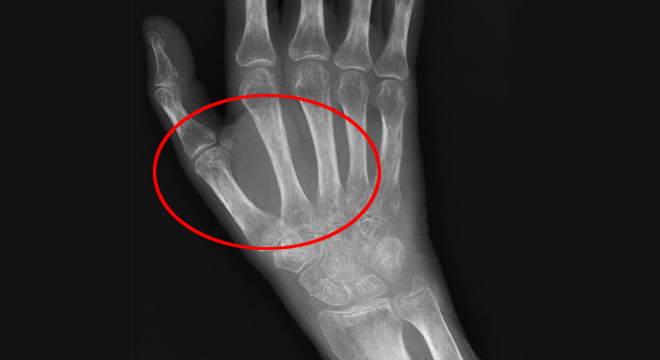

• Knochenschwund /Osteoporose: ist nur im Röntgenbild sichtbar.

Morbus Sudeck: Weichteilausdehnung im Röntgenbild

• Röntgen, Computertomographie, Magnetresonanz: damit können Knochenentkalkungen aufgezeigt werden